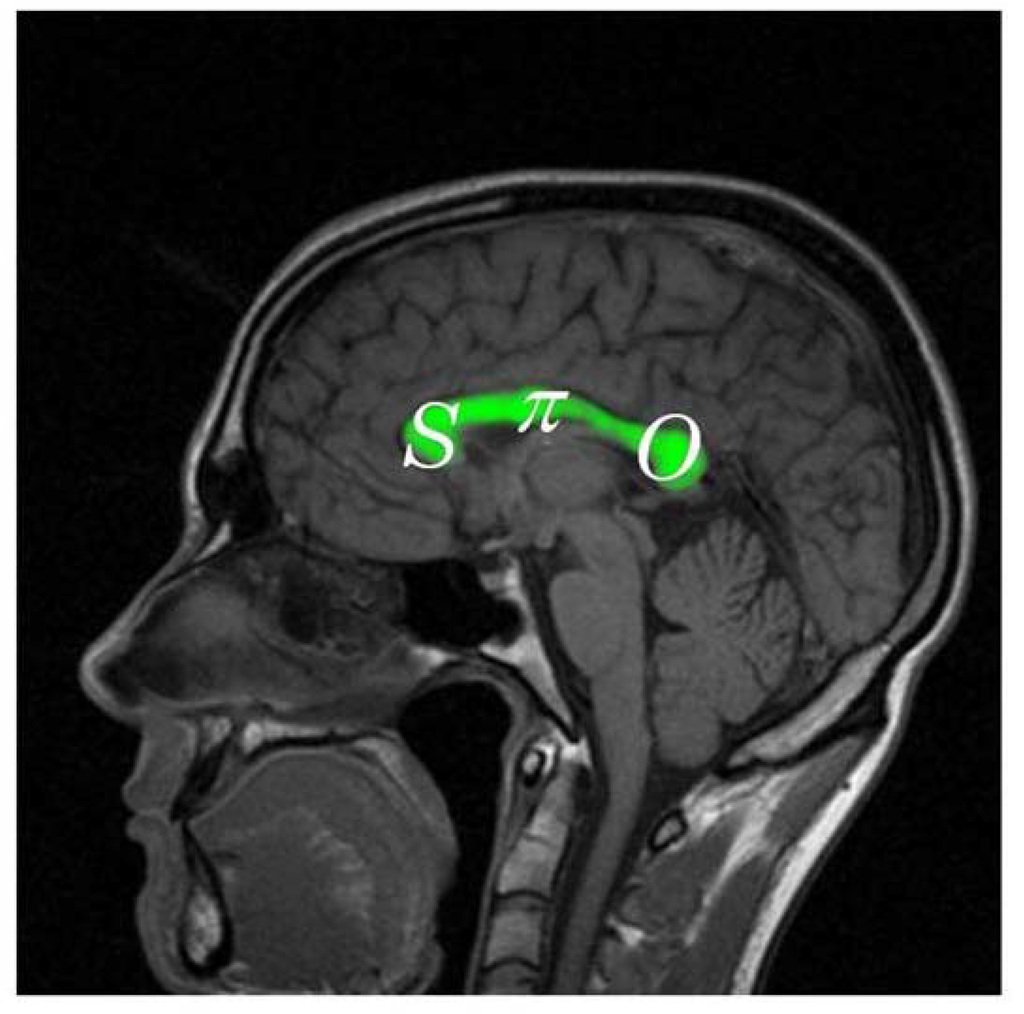

Furthermore, we must suppose that the development of the normal mapping of neurons through the corpus callosum must also reflect the same basic SπO formula as suggested in Figure 5. More specifically we must predict that the rostrum and genu (the bend) at the front of the corpus callosum should be associated with symbolic functions, S; the body of the corpus callosum should be associated with articulate and tactically complex motor sequences (as seen in speaking, writing, typing, and signing), π; and the basic sensory functions involved in constructing icons of objects should be associated with the posterior portion of the corpus callosum, O.

Figure 5.

The pragmatic mapping relation (in white lettering) hypothesized in the neuroarchitecture of the corus callosum (colored in green).

Until recently, with the development of diffusion tensor magnetic resonance imaging (dMRI)—e.g., see Paul, et al. [57] as well as Hofer and Frahm [58]—the inferences of Figure 5 could only be tested against symptomatic observations of persons with focal lesions in the corpus callosum. However, with dMRI it has become possible to map the estimated 190 million axons extending from the neuronal bodies extending from various regions of the cortex through the corpus callosum to the highest level of the neurons of the opposite hemisphere of the cortex as shown in Figure 6. The mapping actually found is indeed consistent with the formula, SπO. Also, as we should expect, focal lesions in the corpus callosum produce symptoms consistent not only with inferences at the global level of neuroarchitecture suggested in Figure 3, but also with considerably more specific predictions flowing from the hypothesized architecture of the corpus callosum suggested in Figure 5 and borne out in Figure 6.